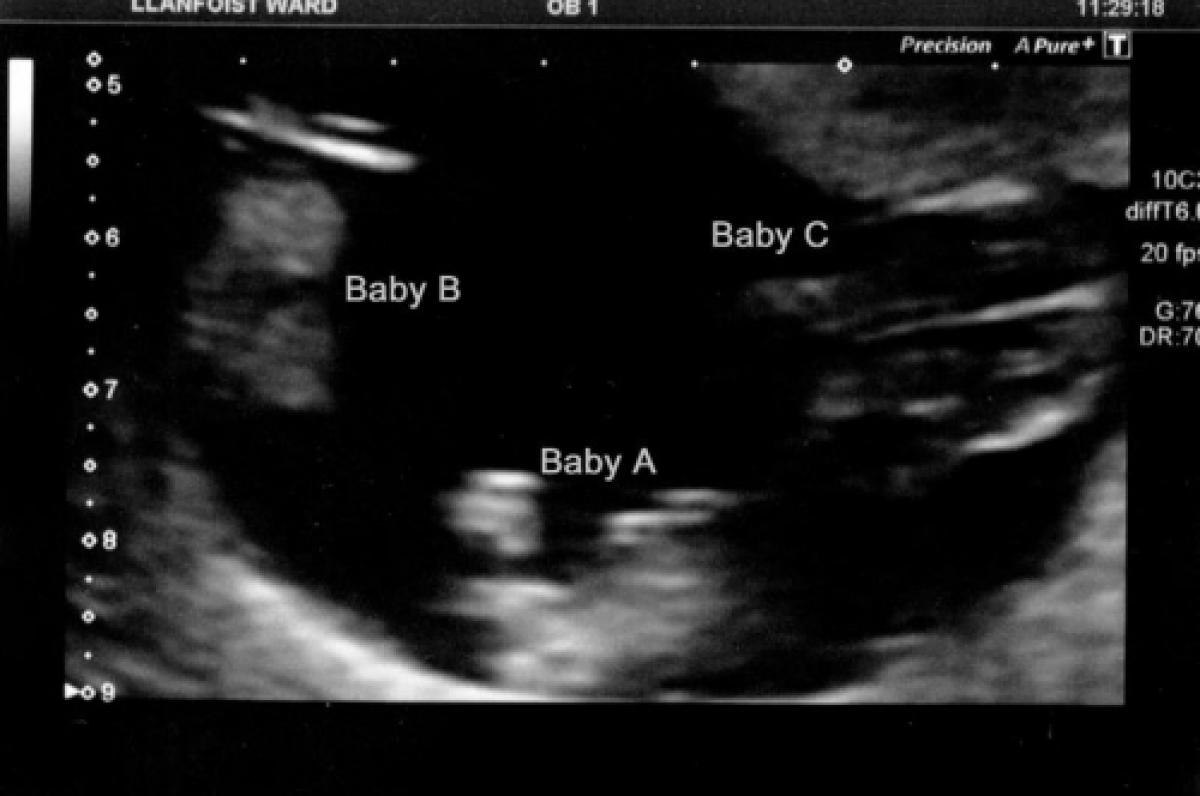

Ashley Alexander, o femeie din SUA a adus pe lume trei gemene identice, un caz extrem de rar care i-a uimit pe medicii care au supravegheat sarcina.

Fetițele au fost concepute într-un mod natural și au venit pe lume la 36 de săptămâni, complet sănătoase.

Vestea că vor avea trei fetițe a venit pe neașteptate pentru Ashley și Matt. “L-am întrebat pe medical de la ultrasunete dacă glumește și mi-a răspuns: Domnule, noi nu glumim cu așa ceva”, a povestit proaspătul tătic.

Șansele de a concepe tripleți identici, fără a urma un tratament de fertilizare, sunt extrem de rare, specialiștii apreciind că pot fi de una la 200 milioane.